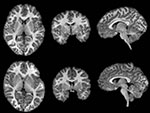

In the current study, researchers examined brain images in preschoolers (ages 4 and 5) both with and without symptoms of ADHD, specifically looking at cortical and basal ganglia volumes and the size of these particular areas of the brain. Researchers analyzed high resolution MRI brain images in 26 preschoolers, 13 presenting with ADHD symptoms and 13 without, and found differences in the caudate nucleus.The caudate nucleus is a small structure in the subcortical region of the brain and is associated with cognitive and motor control. Results showed that children with ADHD symptoms had significantly reduced caudate volumes compared to the children who did not present with ADHD symptoms. Additionally, these caudate volumes were significantly correlated with parent ratings of hyperactive/impulsive symptoms. Cortical volumes, however, were not associated with symptom severity. Researchers concluded that differences in basal ganglia development, particularly the caudate nucleus, appear to play an important role among children presenting with early onset symptoms of ADHD.